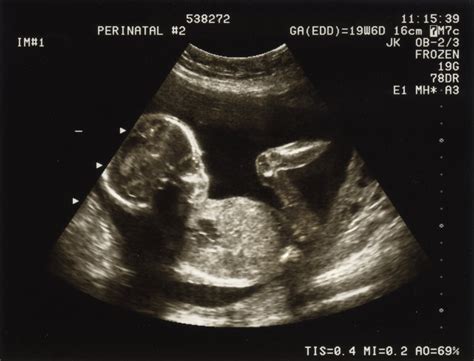

Un alt moment-cheie este morfologia fetală de trimestrul II, o ecografie detaliată care evaluează organele bebelușului, dezvoltarea sistemelor vitale și eventualele malformații.